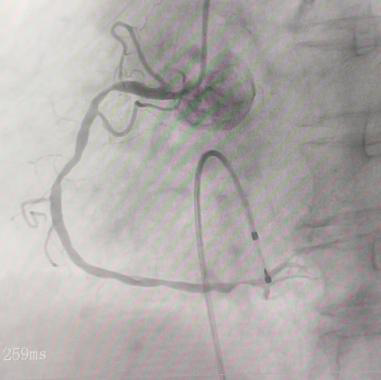

内一科学科带头人李绍波主任在介入室为患者实施了临时起搏器置入术,并同步进行冠脉造影。结果显示,患者冠状动脉存在多处严重狭窄。李绍波主任随即进行药物球囊扩张和支架植入,成功疏通血管,恢复血流。术后,患者生命体征平稳,心率逐渐恢复正常,心电图也未见异常。

术前 术后